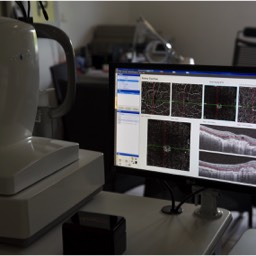

Ci-dessous on voit des néovaisseaux dus à une Dégénérescence Maculaire Liée à l'Age (DMLA). Les rétinophotographies sont réalisées avec l'appareil Eidon de la société italienne CenterVue, et l'OCT angiography est réalisée avec l'OCT de la société américaine Optovue.